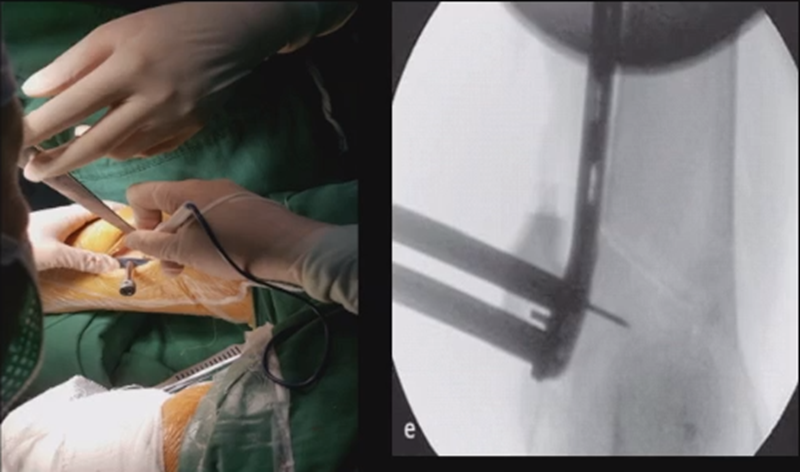

术中发现螺钉松动,截骨端出现坎插迹象。

近端螺钉松开,调整力线,重新固定后,在外侧加小钢板抗旋

术后10周复查,力线较好。